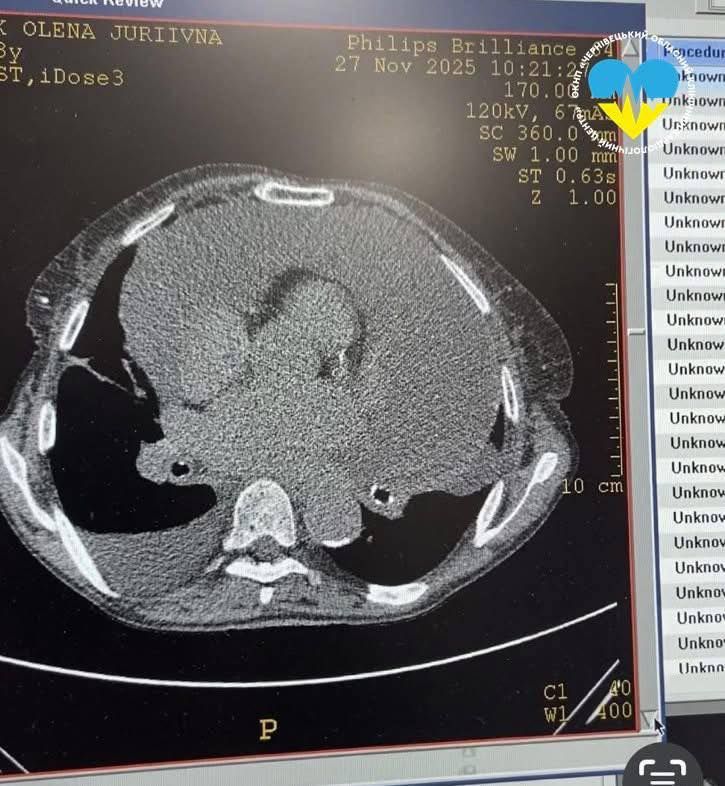

На фото МРТ видно навколосерцеву сумку з рідиною

До лікарні мешканка Путильської громади потрапила із сильною задухою, повідомили у понеділок, 8 грудня, на сторінці Чернівецького обласного клінічного кардіологічного центру в фейсбуці. За словами жінки, нормально дихати вона не могла вже понад два місяці. Щоб встановити причину, пацієнтці провели комплексне обстеження: ехокардіографію, рентген та комп’ютерну томографію органів грудної клітки.

Через погіршення стану пацієнтки лікарі провели процедуру відведення зайвої рідини через встановлений у перикард катетер. Під час втручання з порожнини перикарда було видалено 2 л 400 мл рідини. Після цього стан жінки значно покращився. Для контролю її здоров’я медики повторно провели ехокардіографію та комп’ютерну томографію, щоб оцінити стан перикарда та з’ясувати причину виникнення небезпечної ситуації.